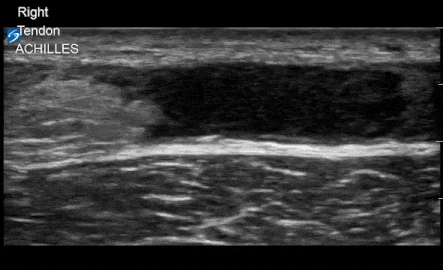

This can be visualized in both a short and long view. Pain in the tendon, good story plus ultrasound can be diagnostic. Track the tendon down using the probe. Here’s the long view with an intact and ruptured tendon.

Here’s the short view.